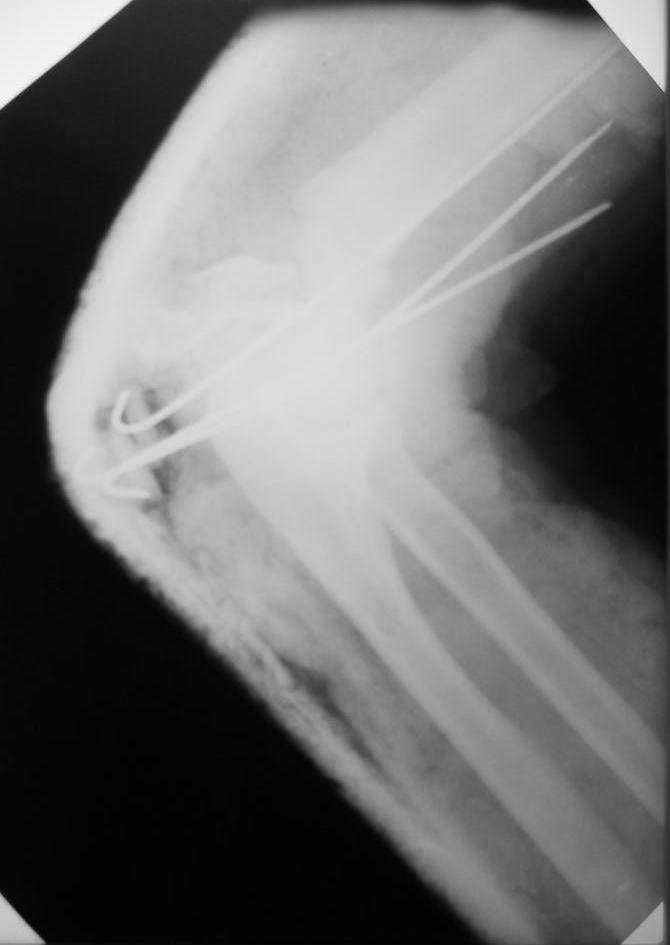

больная Ч. 24 года. Поступила в отделение после ДТП 15.01.08 при поступлении о/с костей таза АВФ. О/с лев плечевой кости спицами. На данный момент состояние больной ближе к удовлетворительному. С переломом костей голени особых вопросов нет. Хотелось бы услышать ваше мнение.